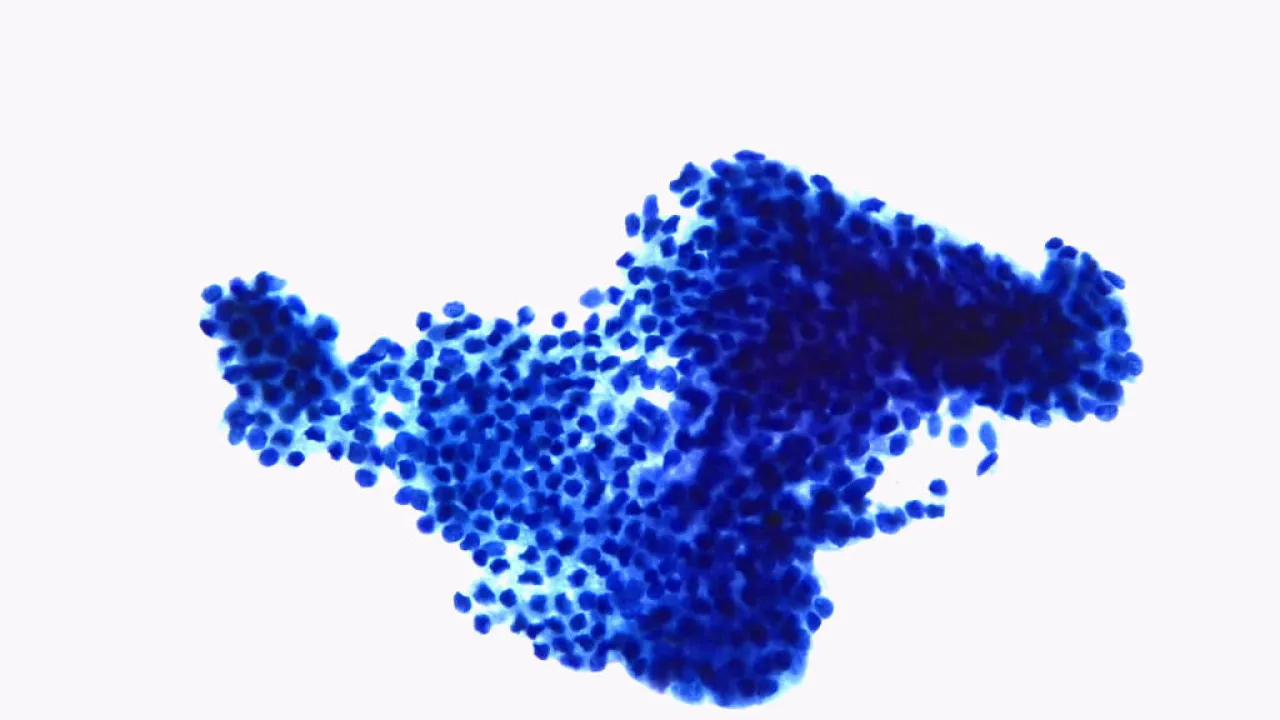

Lymph nodes, Small lymphocytic lymphoma/Chronic lymphocytic leukemia, CD20 stain